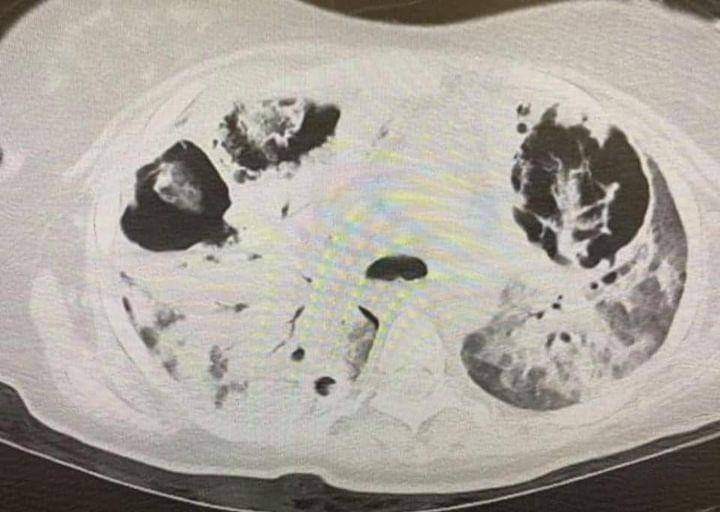

Az alábbi képen egy 25 (!) éves, oltatlan, semmilyen más betegséggel nem rendelkező, COVID-19-ben szenvedő beteg tüdeje. Intenzív osztályon kezelik, 4. hete szorul gépi lélegeztetésre.

Mivel a gépi lélegeztetéssel egyre kevésbé lehet a tüdején keresztül a szervezetébe oxigént juttatni, ún. ECMO-ra kötötték, mely a testén kívül, gép segítségével juttatja a véráramba az oxigént.

Túl van remdesivir, dexametazon és tocilizumab terápiákon, jelentős mennyiségű és fajtájú antibiotikumot kapott a másodlagos fertőzések miatt. Jelenleg napok óta lázas, emiatt mellkasi CT-felvétel készült.

A COVID-19 fertőzés okozta tüdőgyulladás miatt a folyadékkal teli tüdő nem képes elegendő oxigént leadni a vérbe.

Az eredmény magáért beszél. A tüdejében 3 nagy lyuk keletkezett, melyekben hatalmas penészgombanövedékeket lehet megfigyelni. Ez az a penészgomba, ami a kinn hagyott gyümölcsöt és kenyeret is elfogyasztja.

Összehasonlításképp, egy egészséges tüdőről készült mellkasi CT-felvétel, ehhez érdemes hasonlítani a bejegyzés CT-felvételét.

A fekete, finom szürke vonalas szerv a tüdő.  A fekete részek a légtartő tüdő szövetét jelölik.